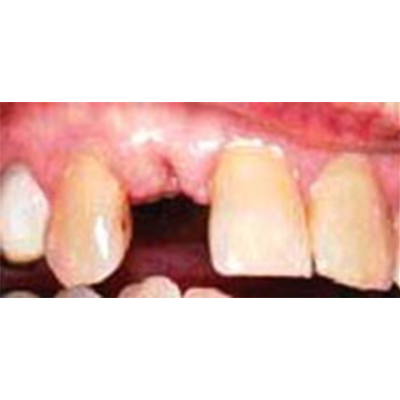

Replacement of a single tooth

If you are missing a single tooth, it can be replaced without having healthy neighboring teeth ground down to support a bridge. Dental implants are a great option for single tooth replacement, especially in the front of the mouth where a good cosmetic result is so important. Here are some examples of patients who have benefited from dental implants.